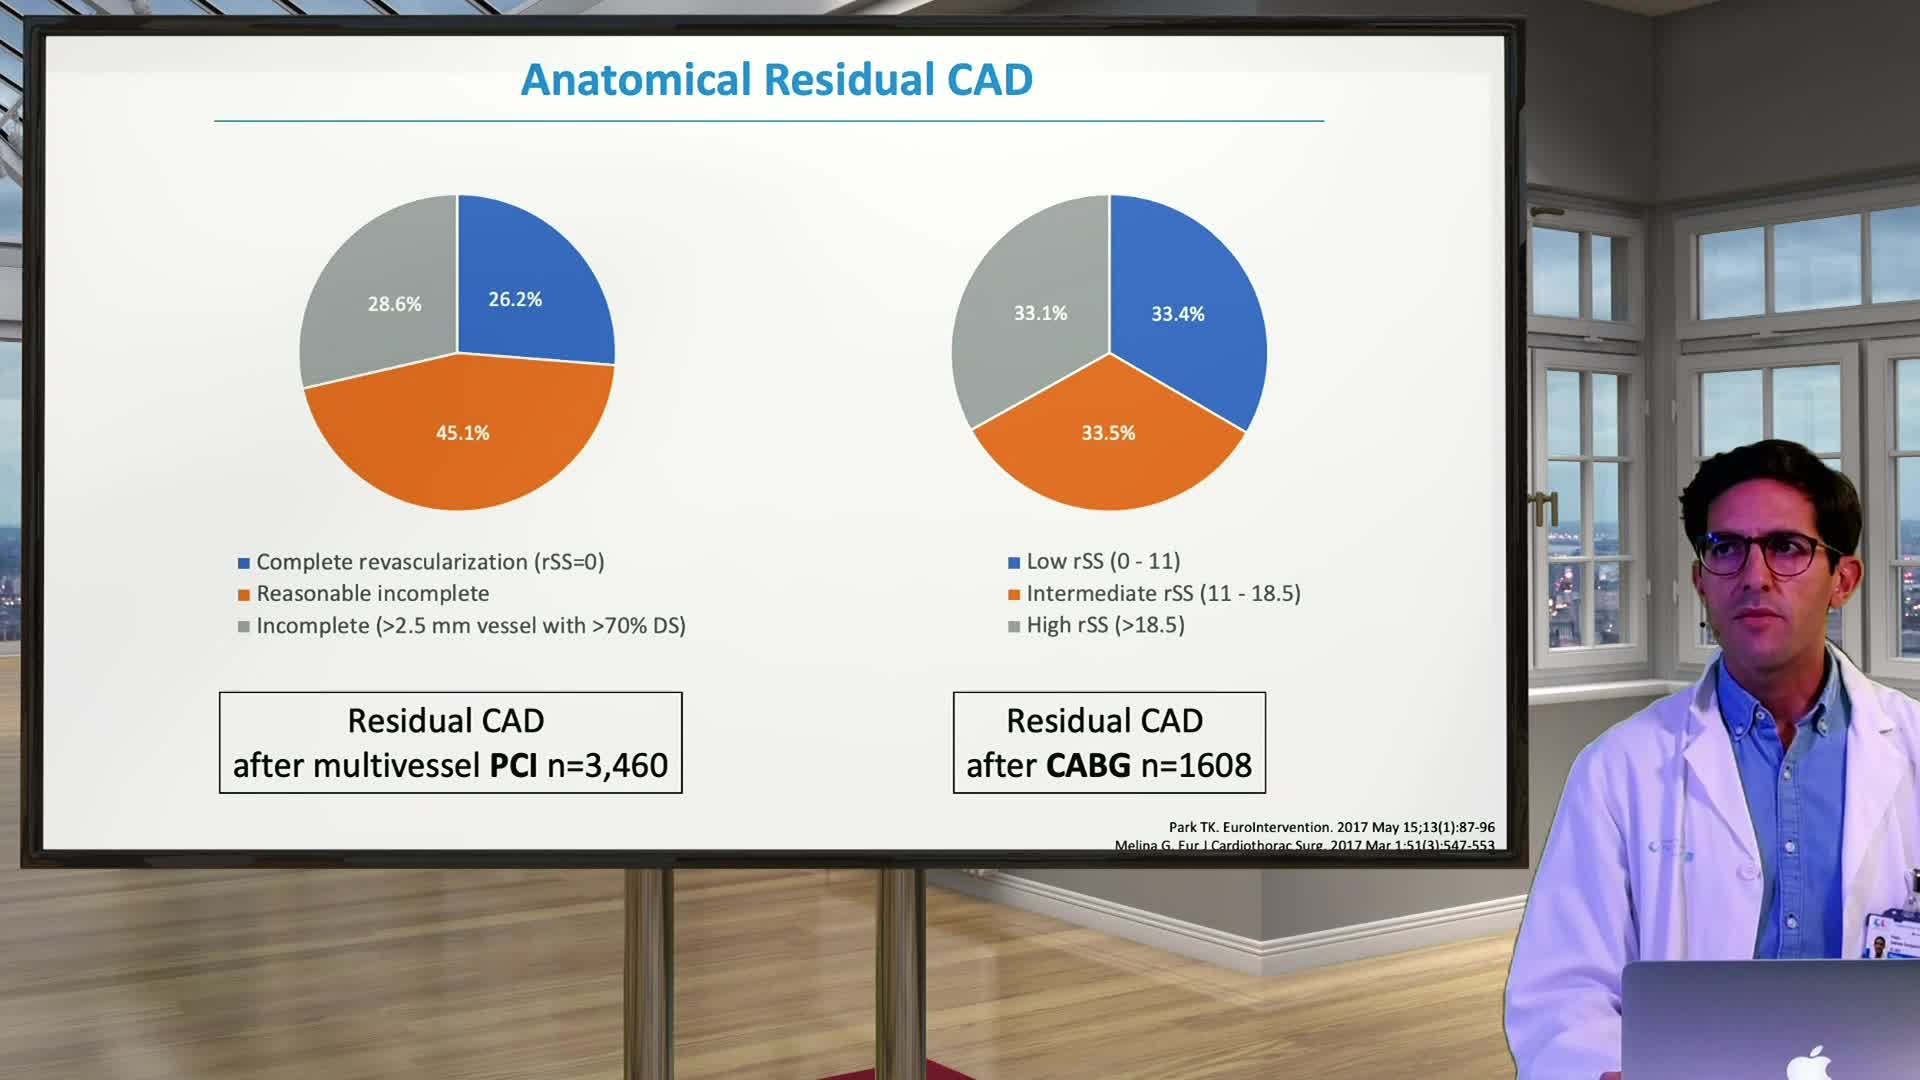

Spotlight Discussion: Management of multivessel disease in patients with acute coronary syndromes